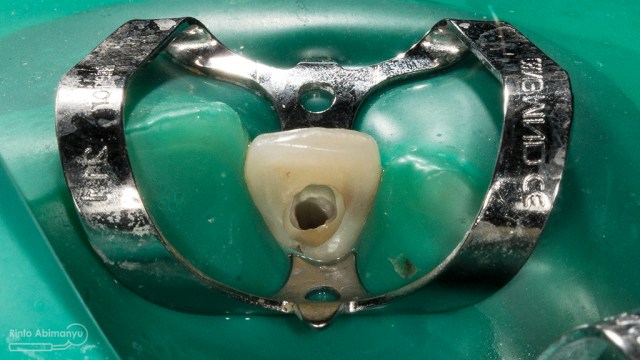

Untuk kunjungan pertama ini saya rencanakan melakukan perawatan saluran akar langsung pada dua gigi central… Saya pasang rubber dam untuk mengisolasi daerah kerja

Gigi 11 21 setelah dipasang rubber dam